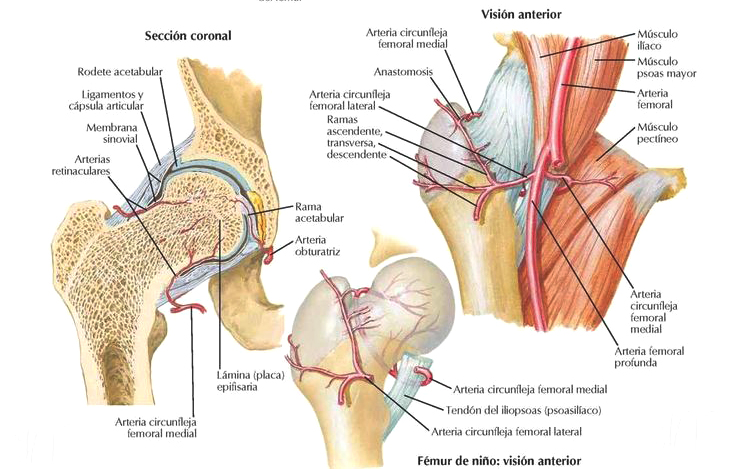

Teoría Vascular: Vascularización de la cabeza femoral en el niño. El aporte sanguíneo del cabeza femoral pediátrico se realiza a través de una pequeña contribución de la arteria del ligamento redondo que es rama de la arteria obturatriz y fundamentalmente a través del anillo vascular cervical extracapsular. Estos vasos atraviesan la capsula articular y la sinovial y se convierte en vasos intraóseo que origina el anillo vascular subsinovial del que parten arterias que atraviesan el cartílago hialino que rodea el núcleo epifisario y forman arcadas que irriga la totalidad de la cabeza femoral.4

Estudios angiográficos han demostrado la obstrucción de las arterias capsulares superiores en la cabeza femoral en los pacientes con la enfermedad de Perthes, así como una reducción general del flujo sanguíneo con descenso significativo de la arteria circunfleja medial5.